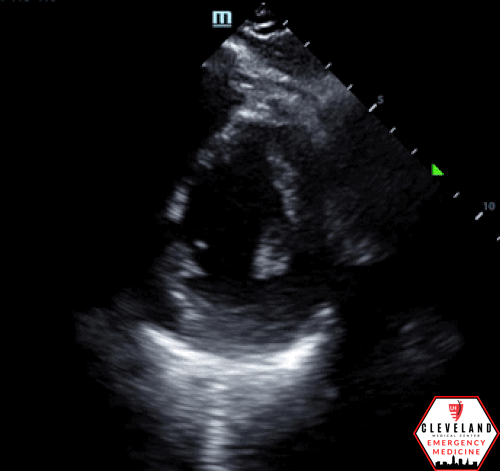

LV function is preserved, there’s no pericardial effusion or signs of right heart strain. There is, however, a large left atrial aneurysm, best seen in the apical 4 chamber view and especially in the subxiphoid view. When color doppler was applied, there was no significant mitral (or other valvular) regurgitation or abnormalities. No prior images to compare.